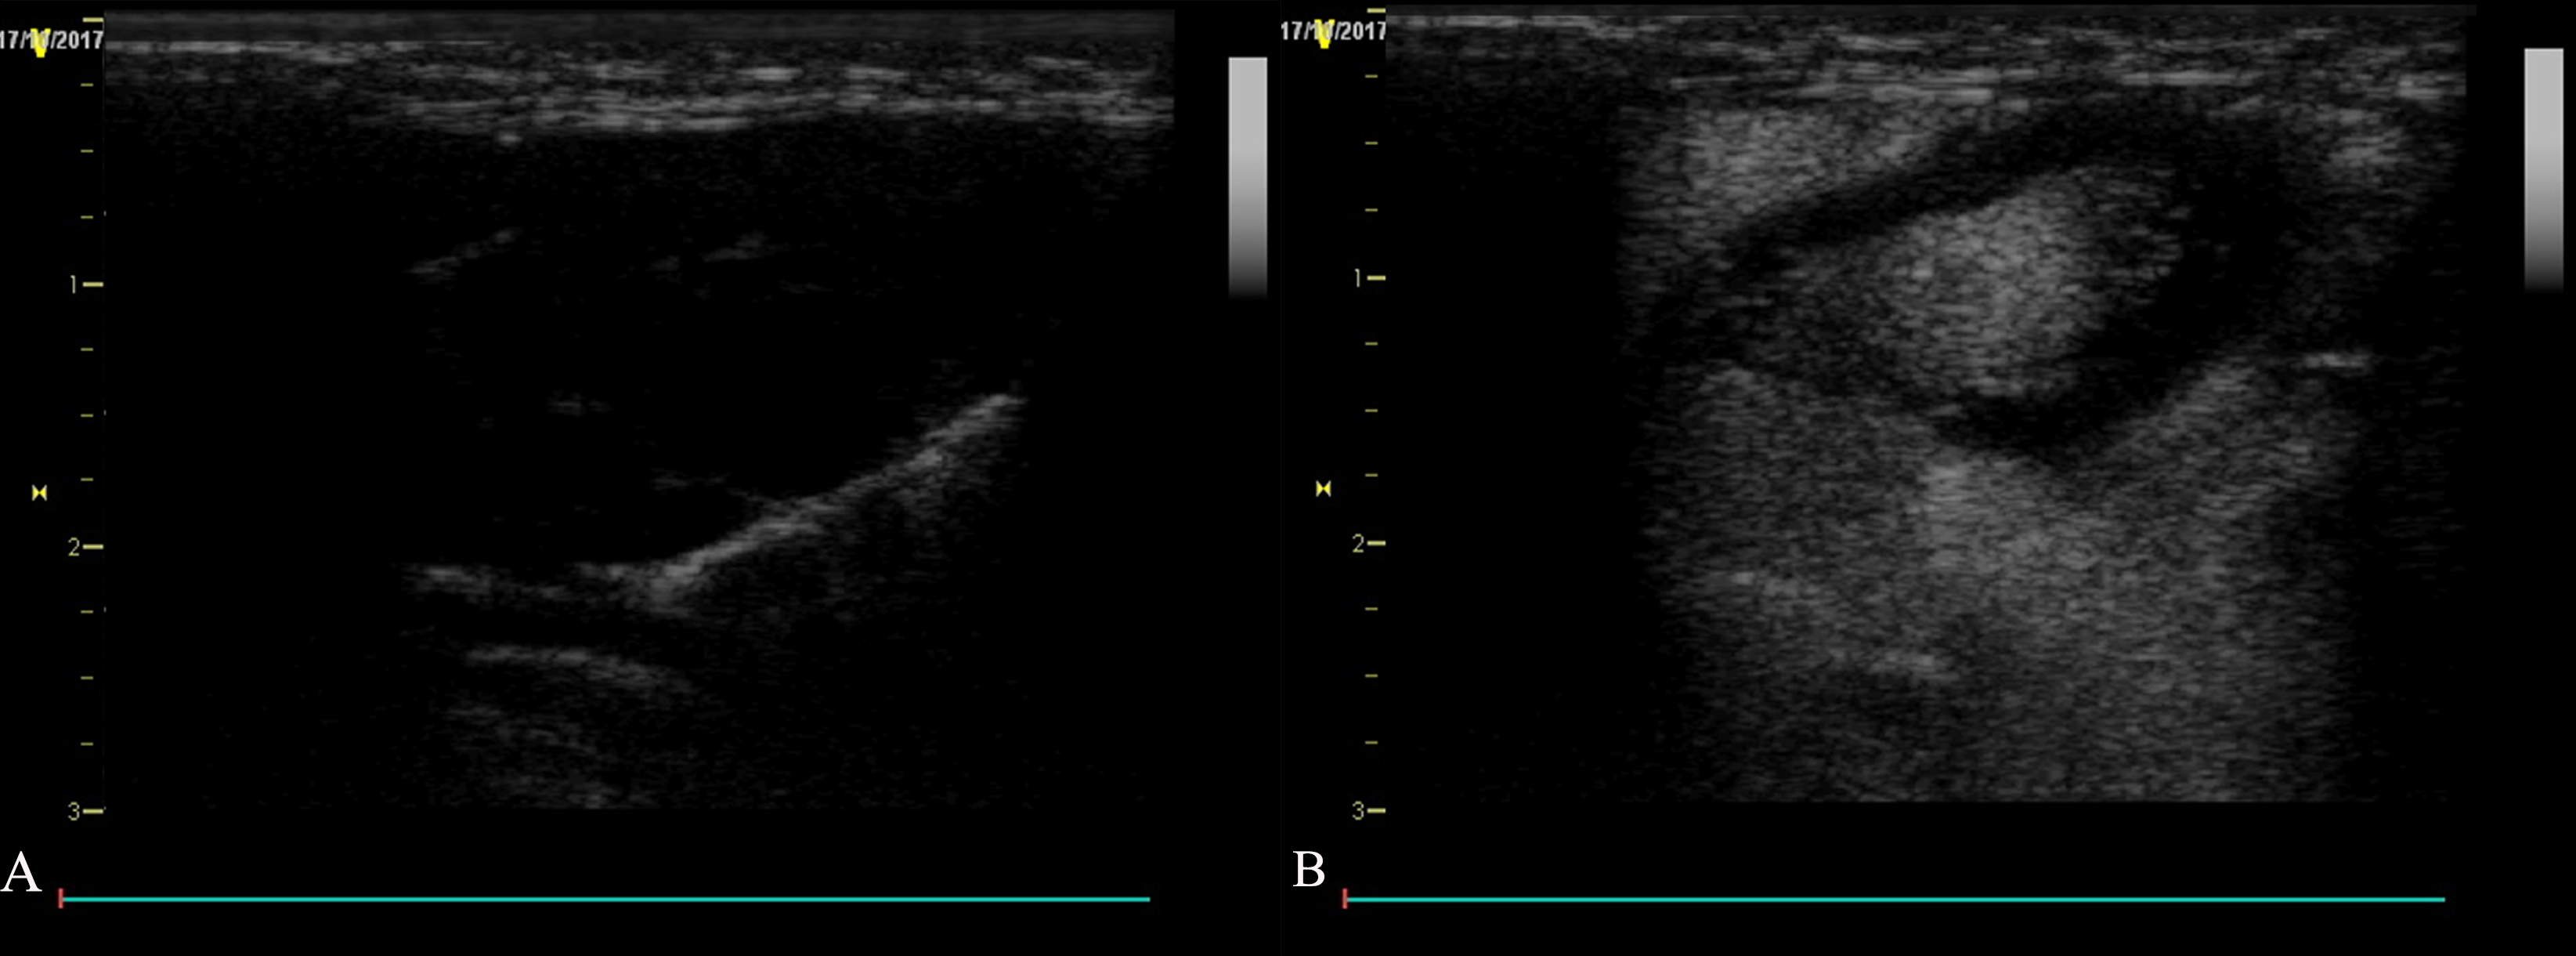

After the injection of the ultrasound contrast agent, contrast agent signal was observed in the carotid lumen at 3 seconds after injection in the four groups except for the control group (Fig. 6). The arrival time inside the plaque was later than that of the the carotid lumen, and strengthening began at the plaque base and gradually progressed to the more internal portions or short linear strengthening, which was predominantly level II or level III. After the enhancement lasted for several minutes, the enhancement effect at the plaque gradually weakened, and the contrast agent gradually cleared.

Fig. 6.Rabbit carotid artery contrast-enhanced ultrasound. (A) Image showing the anti-VCAM-1 nanometer contrast agent group with short linear enhancement in the plaque. (B) Image showing the nanoscale contrast agent group with dot enhancement in the plaques. (C) Anti-VCAM-1 sonovi group. (D) SonoVue group; dot enhancement was observed in all plaques. (E) Control group; no contrast agent sonogram is observed in the lumen.

There was a statistically significant difference in the arrival time of the

plaques between group A and group B (p